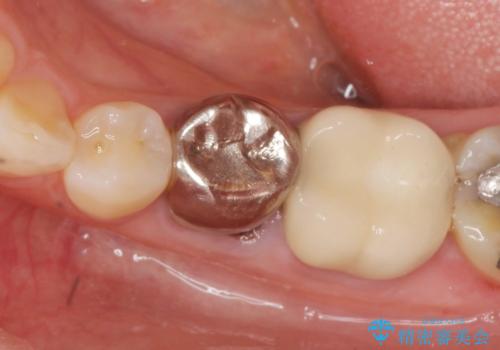

- 大人になってからも残っていた乳歯が揺れ始め、抜歯を覚悟しインプラント治療を希望して来院されました。

X線写真より、乳歯は抜歯が必要な状態でインプラントは小臼歯の埋伏により難しい状況であったのでブリッジによる補綴を選択しました。

ブリッジ治療の予知性を高めるために、虫歯の徹底的な除去に加え縁上歯質を確保するための歯周外科手術、マイクロスコープを用いた精密根管治療を行う治療計画としました。